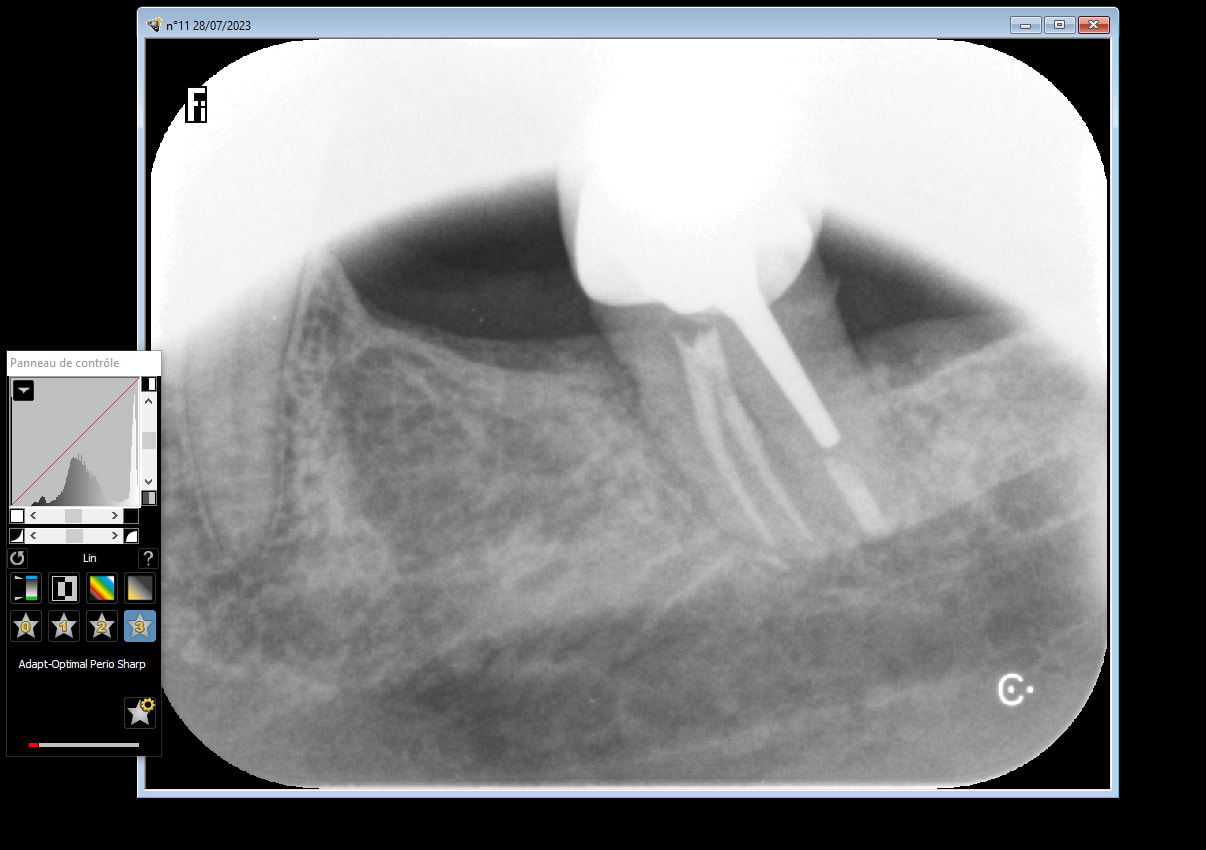

28/07/2023 à 11h01

bon , je viens de recevoir mes nouvelles pellicules molles , et effectivement c est plus net .

j en ai profité pour te prendre une nouvelle radio de cette dent extraite nettoyée et replacée .

Ci joint la radio.

28/07/2023 à 11h04

et donc à ta question de comment je savais qu il y avait un kyste ? ben pcq je l ai vu quand j ai enlevé la la dent :-) , tout simplement .